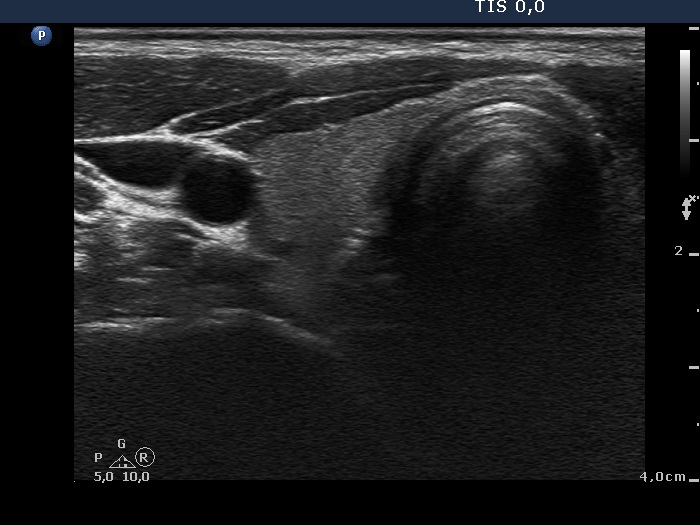

Follow-up examination 11 months later (3rd row of images):

Clinical presentation: The patient had no complaints.

Palpation: no abnormality.

Functional state: euthyroidism with TSH 1.09 mIU/L, and FT4 17.1 pM/L.

Ultrasonography: The thyroid was echonormal with several small minimally hypoechogenic areas. The vascularization was less than the average.